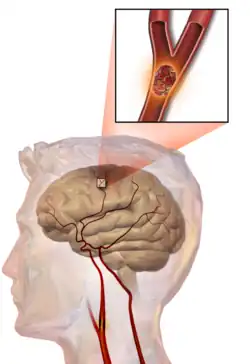

Cévní mozková příhoda (CMP, též ictus, iktus, mozková mrtvice nebo mozkový infarkt) je náhle se rozvíjející postižení určitého okrsku mozkové tkáně vzniklé poruchou jejího prokrvení. K této poruše může dojít buď na podkladě uzávěru mozkové tepny (tzv. ischemická CMP, obrázek 1a,2a), nebo na podkladě krvácení z mozkové cévy (tzv. hemoragická CMP, obrázek 1b,2b). Cévní mozková příhoda je akutní stav, vyžaduje neodkladnou lékařskou pomoc. Včasné rozpoznání a okamžitý transport do specializovaného centra je nutný pro záchranu pohyblivosti a řeči pacienta. Během jedné minuty odumírají miliony buněk. Doprava, diagnostika a léčba proto na sebe musí navazovat v minutách. Pokud se jedná o krevní sraženinu a její rozpouštění – trombolýza – začne do 60 minut po vzniku příznaků, pacient má 70% naději na úplné uzdravení.